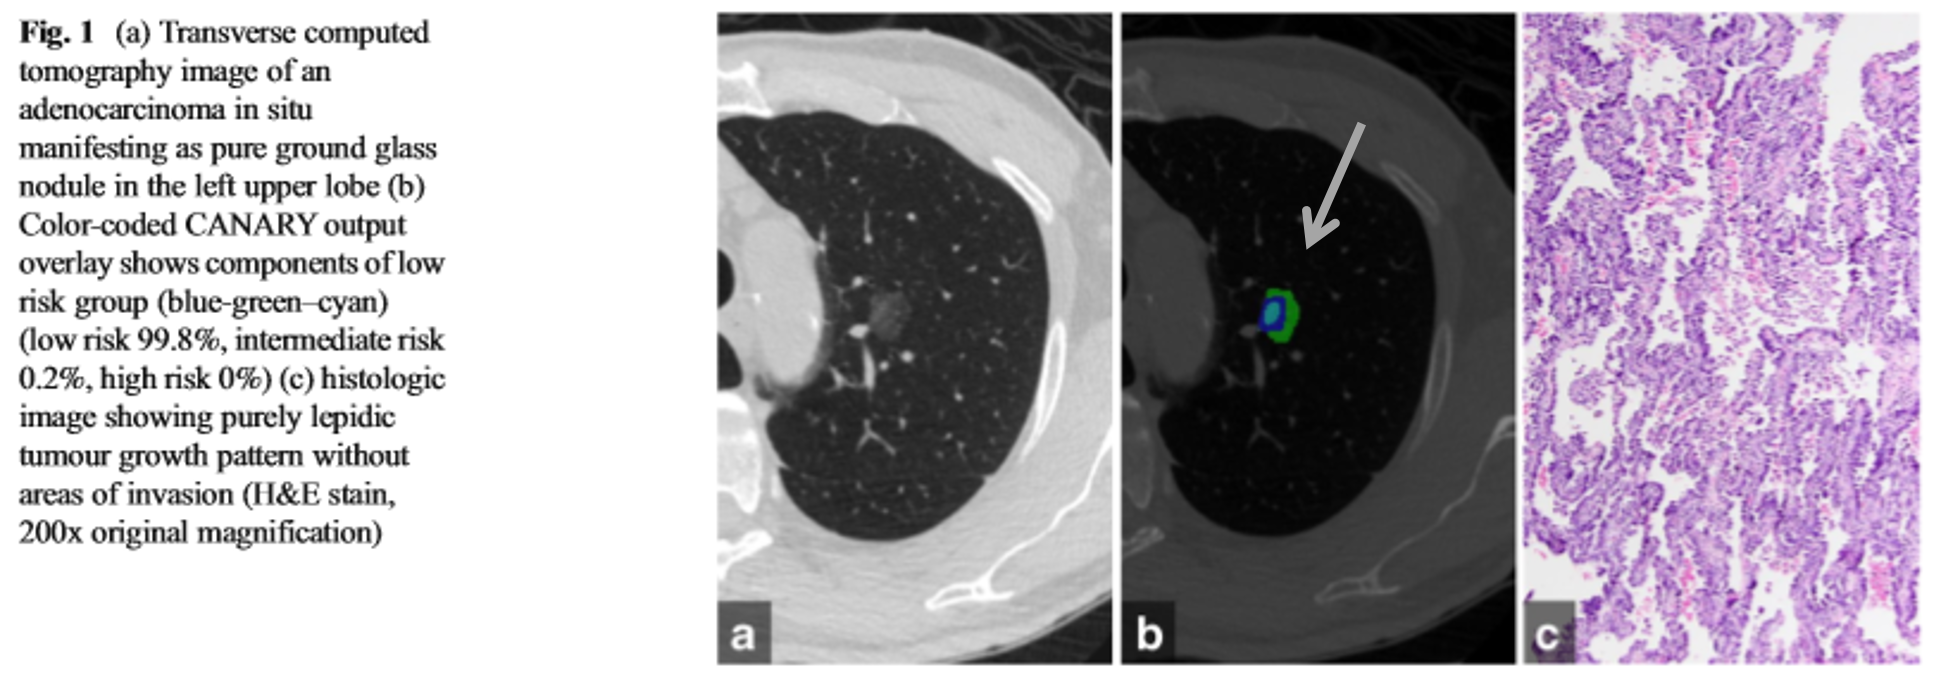

이 연구는 “Computer Aided Nodule Assessment and Risk Yield” (CANARY) software package를 사용했습니다. 이 프로그램은 복셀 농도(voxel density)를 분석하여 폐결절의 위험성(즉, 조직학적 분류)을 예측합니다. 연구는 후향적 연구로, 이미 수술하여 병리적(조직학적)으로 확인된 pure GGO(고형 성분이 안보이는) 결절을 대상으로 했습니다. 이 결절을 다시 두 명의 흉부 전문 영상의학과 의사가 프로그램을 통해 분석하여 대조하였습니다. 여러 기준에 따라, 최종적으로 64개의 병변이 대상이 되었습니다.

프로그램은 결절을 여러 개로 쪼개고, 쪼개진 복셀을 분석하여 9가지 종류의 색깔로 맵핑했습니다. (1) 저위험은 blue-green-cyan, (2)중위험은 pink-yellow, (3)고위험은 violet-indigo-red-orange로 맵핑했습니다.

64개 중에 28개(44%)는 AIS, 26개(41%)는 MIA, 10개(16%)는 IAC였습니다. 3개로 나누어 서로간 맵핑의 분포 차이가 있는지 분석해보았을 때 저위험도 맵핑이 차지하는 퍼센테이지가 AIS>MIA>IAC 순으로 유의하게 차이가 있었습니다. 중위험, 고위험 맵핑의 퍼센테이지는 역순의 유의한 차이를 보였습니다.